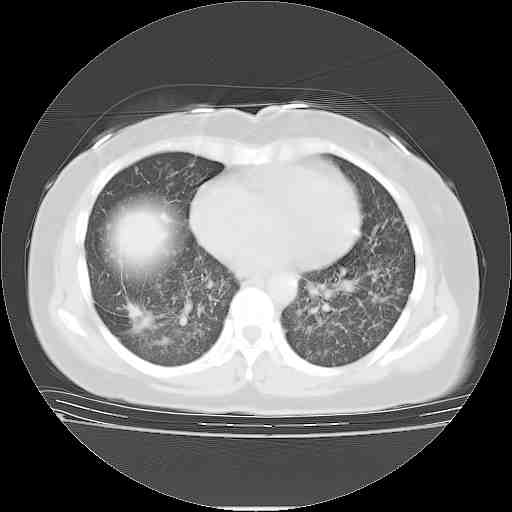

支持右肺下叶周围型肺癌并肺内淋巴管炎,  原发灶小了,但转移较前片明显了.。

支持右肺下叶周围型肺癌并肺内淋巴管炎;病灶有所控制。

支持右肺下叶周围型肺癌并肺内淋巴管炎,  原发灶小了,但转移较前片明显了.